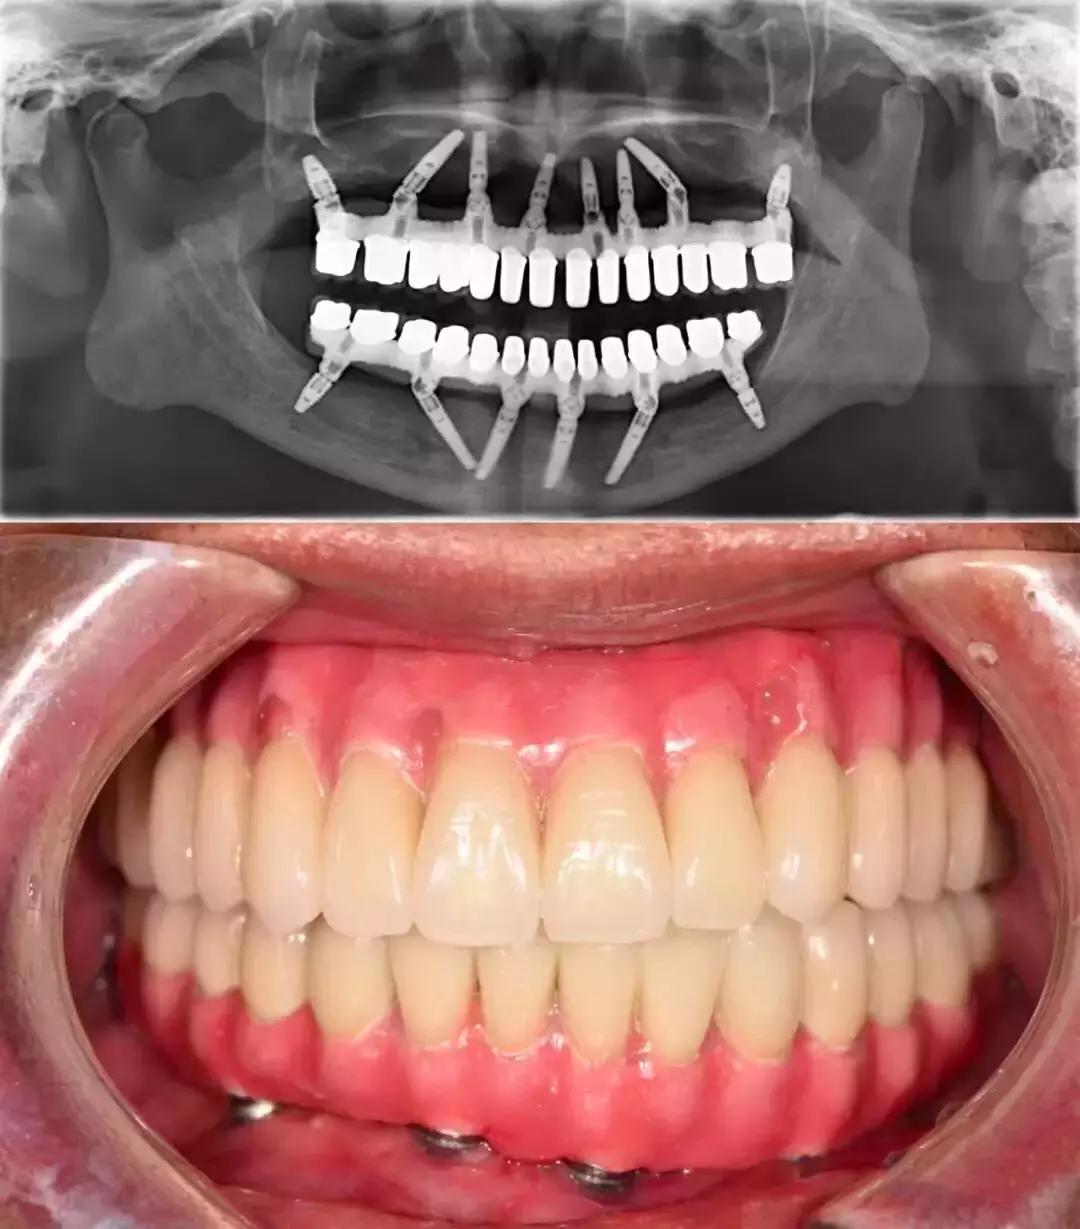

这是一个 30 多岁的小伙子,只是因为「牙齿松动」来就诊。

但等待他的,却是晚期牙周炎患者的最终归宿——全口牙松动,拔除。

@西安牙医老聂 供图

换句话说,他看起来一颗牙也不缺,但其实一颗牙也没有了——这就是晚期牙周炎患者面对的「无牙窘境」。

殊不知全*活口**动义齿,不仅功能比天然牙齿相差一大截,咀嚼效力不高,使用也不方便。全口种植义齿也是一种选择,可以较好地恢复咀嚼功能。

但现实是,并不是每个无牙患者,都拥有「口腔里开一辆奔驰」的财力。

全口种植义齿的花费,相当于「口腔里开一台奔驰」(@种牙匠黄建生 供图)